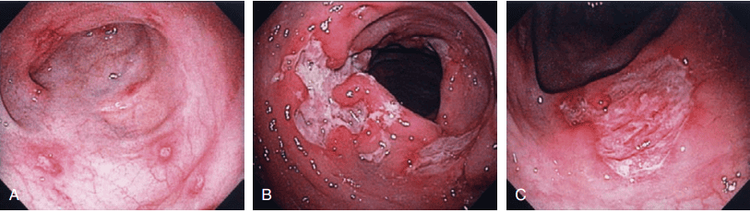

Hình ảnh loét đại tràng đa ổ do bệnh Crohn